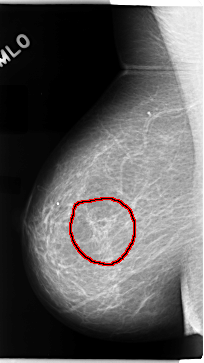

FILE: C_0073_1.RIGHT_MLO.OVERLAY

TOTAL_ABNORMALITIES 1

ABNORMALITY 1

LESION_TYPE MASS SHAPE ARCHITECTURAL_DISTORTION MARGINS N/A

ASSESSMENT 3

SUBTLETY 1

PATHOLOGY MALIGNANT

TOTAL_OUTLINES 1

BOUNDARY